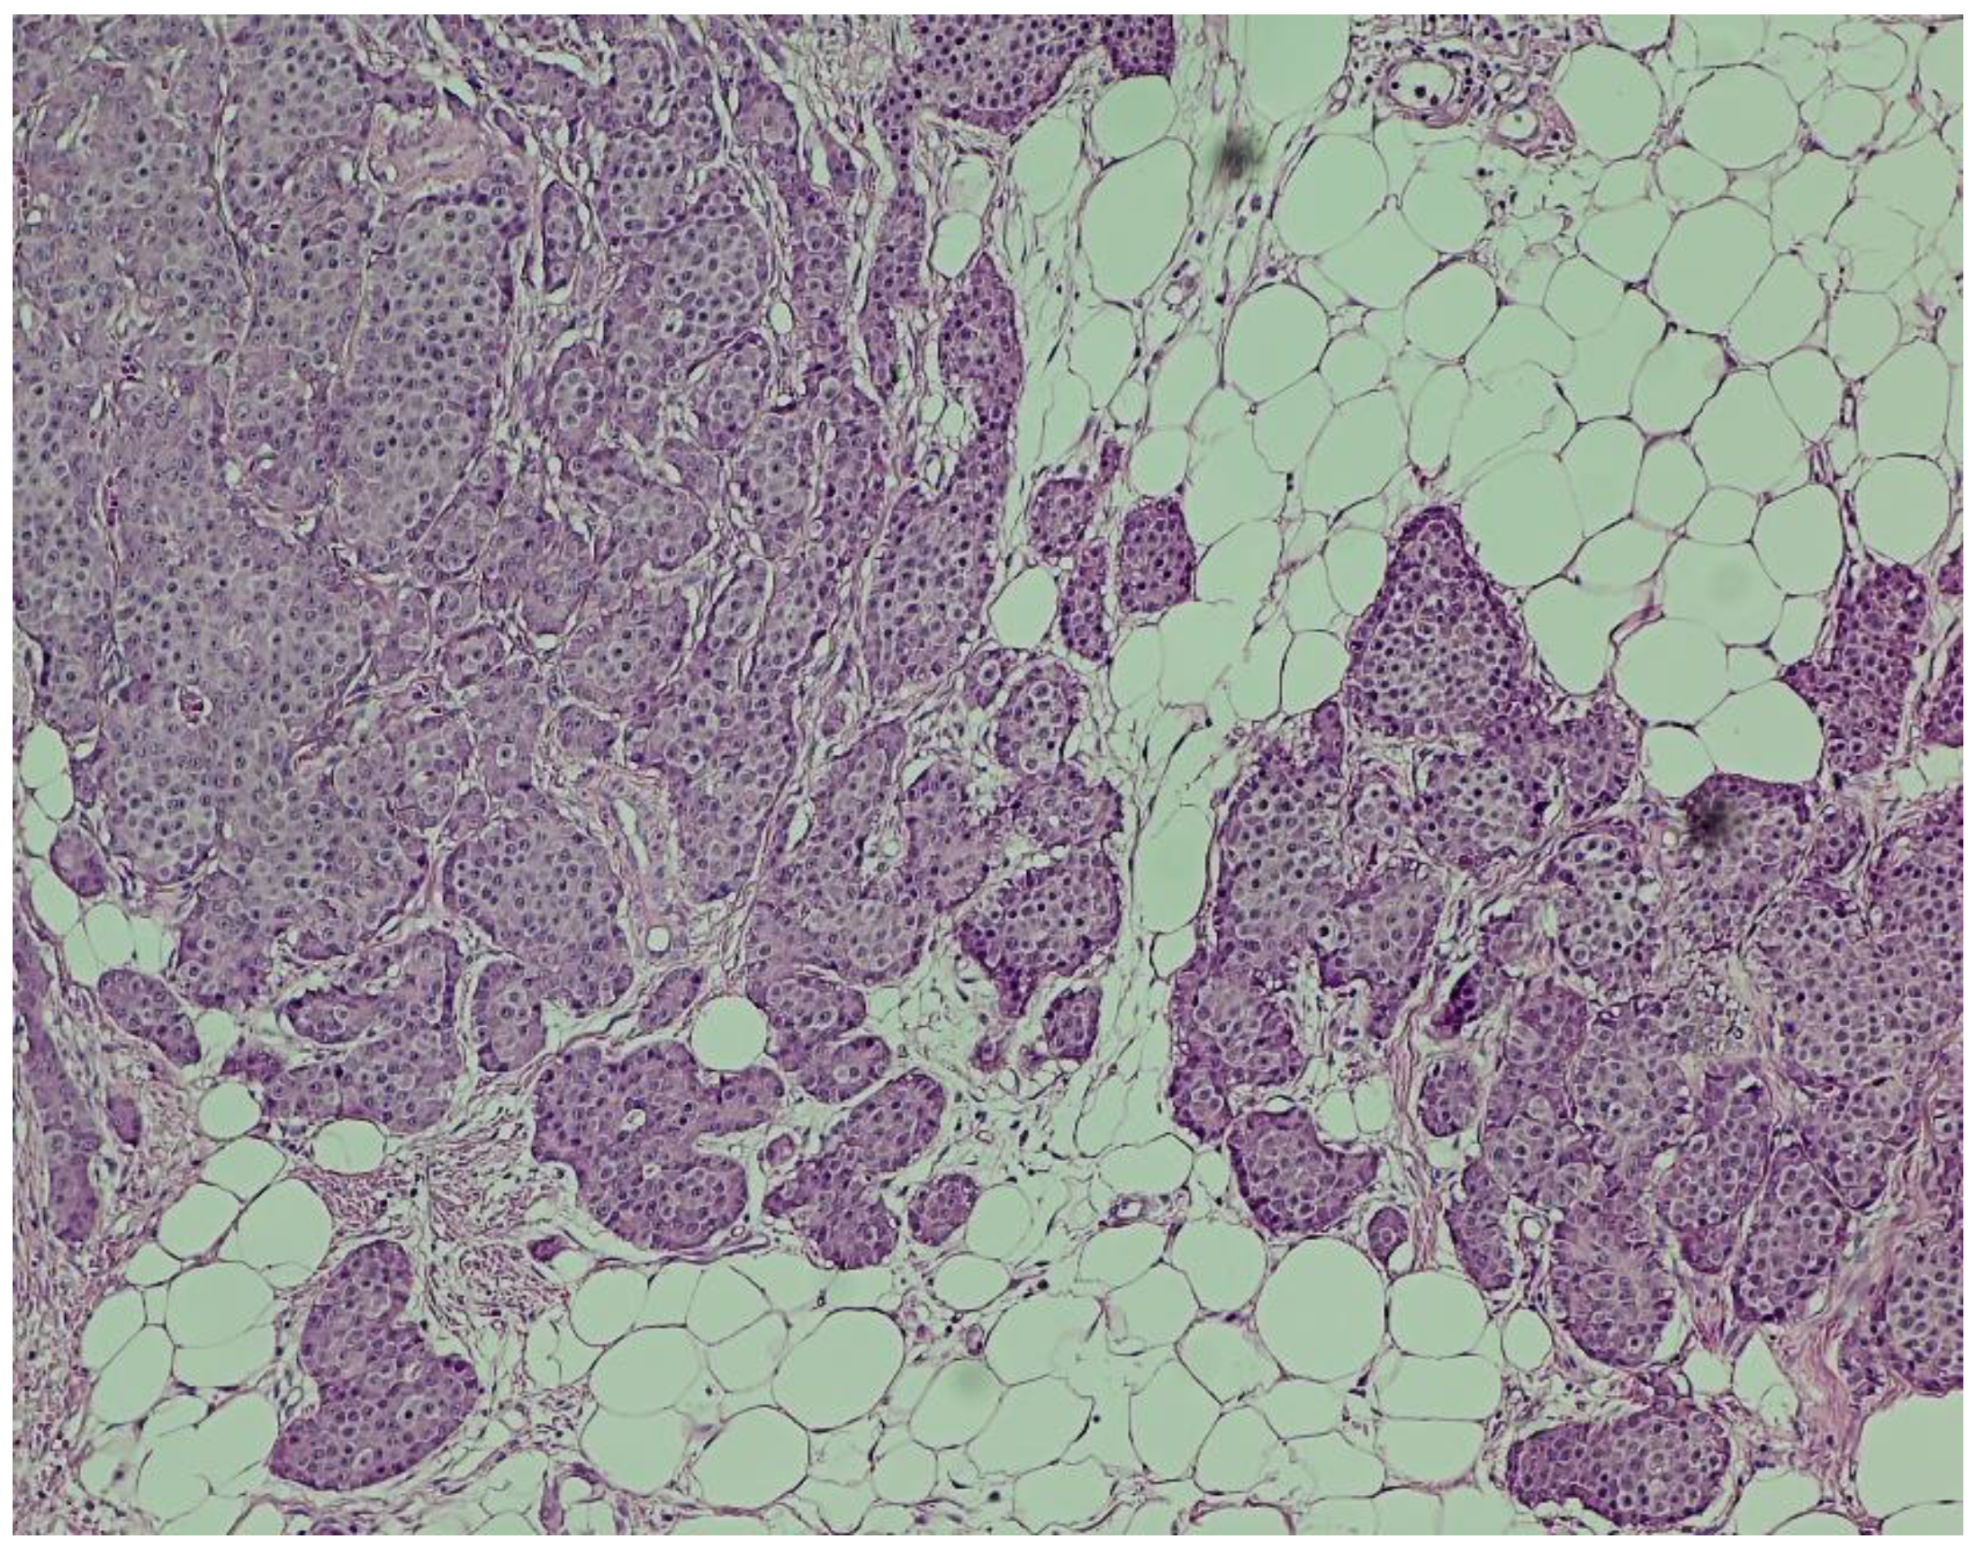

Hematoxylin and eosin (H&E) staining revealed a diffuse proliferation of tumor cells within adipose tissue, predominantly arranged in nested and insular patterns, with focal areas of trabecular architecture. The neoplastic cells were uniform in appearance, displaying round to oval nuclei, finely granular “salt-and-pepper” chromatin, and scant eosinophilic cytoplasm (Figure 4). Mitotic figures were rare (fewer than two per ten high-power fields), and no areas of tumor necrosis were identified—features consistent with a well-differentiated neuroendocrine tumor.

Figure 4. Hematoxylin and eosin (H&E) staining (×100). Nests of uniform neuroendocrine tumor cells exhibiting round nuclei, “salt and pepper” chromatin, and minimal cytological atypia, consistent with a well-differentiated morphology.